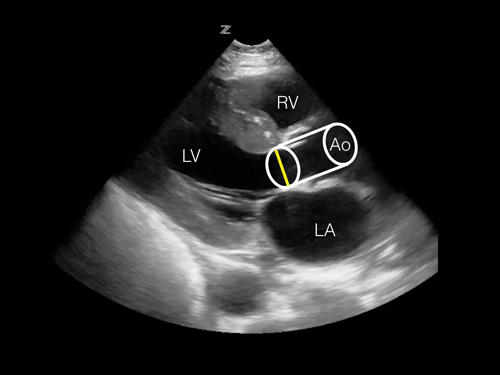

- Đường kính LVOT (đường ra thất trái) tại van động mạch chủ ở mặt cắt trục dọc cạnh ức, ta tính được diện tích hình tròn = π x (đường kính LVOT÷2)2

- Đặt đầu dò tại vị trí trục dọc cạnh ức

- Phóng to(Zoom) đến LVOT (đường ra thất trái hay van động mạch chủ).

- Đo đường kính LVOT lúc van động mạch chủ mở hết(tối đa).